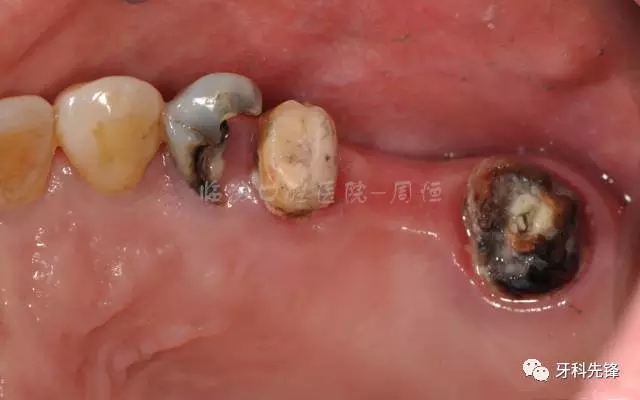

患者:郭某某女55歲

主訴:右上后牙修復(fù)體崩瓷,松動兩個月左右

現(xiàn) 病 史:患者兩個月前右上后牙修復(fù)體邊緣不密合,松動崩瓷,近期不適加重要求重新修復(fù),來診

檢查:15 16 17 烤瓷冠修復(fù)體,崩瓷,邊緣不密合,食物嵌塞,齦下牙石II°,冷熱診無不適,叩診(+),牙齦輕微紅腫。

14  殘冠,位于齦下2mm,牙齦顏色正常,叩診(-)

46  頜面充填體近中有懸突,PD:10mm,根分歧III°,陰影較大,叩診(+),牙齦輕微紅腫。

圖2  術(shù)前側(cè)位咬頜照

圖3 術(shù)前頜面照